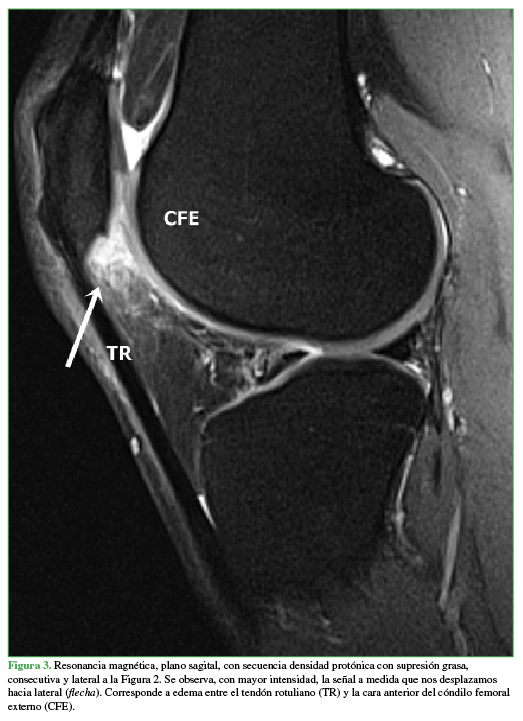

PropiaLuego se le realizó una resonancia magnética (RM) (Figuras 2,3,4,5,6) que mostró como hallazgo central la presencia de hiperintensidad en las secuencias líquido sensibles indicativa de edema en el sector superolateral del paquete adiposo infrarrotuliano (PAI) o de Hoffa. Se constató un desgarro degenerativo en el menisco externo y pequeños quistes parameniscales asociados, así como condromalacia rotuliana de bajo grado (imágenes no mostradas). Las estructuras óseas y ligamentarias eran de características normales.

Se observa, con mayor intensidad, la señal a medida que nos desplazamos hacia lateral (flecha). Corresponde a edema entre el tendón rotuliano (TR) y la cara anterior del cóndilo femoral externo (CFE)

Propia